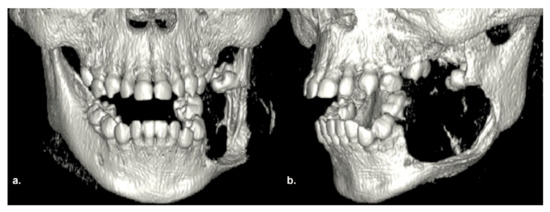

2.1. Clinical and Preoperative Radiological Presentation